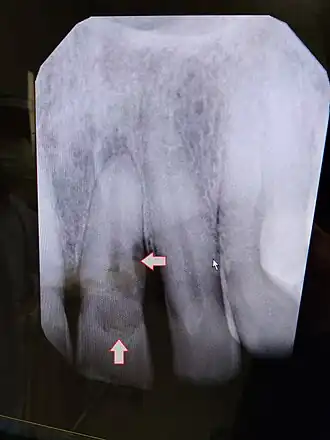

![]() | |

| Post traumatic External tooth resorption 9 | |

External resorption is the loss of tooth structure from the external surface of the tooth and is further subcategorized based on its etiology.[16]

External inflammatory root resorption may be caused by trauma to the root surface, due to damage to the periodontal ligament (PDL) and/or extended drying following tooth avulsion. Following trauma, dentinal tubules are exposed leading to communication with an infective or necrotic pulp. This leads to an inflammatory process that causes external root resorption.[16]